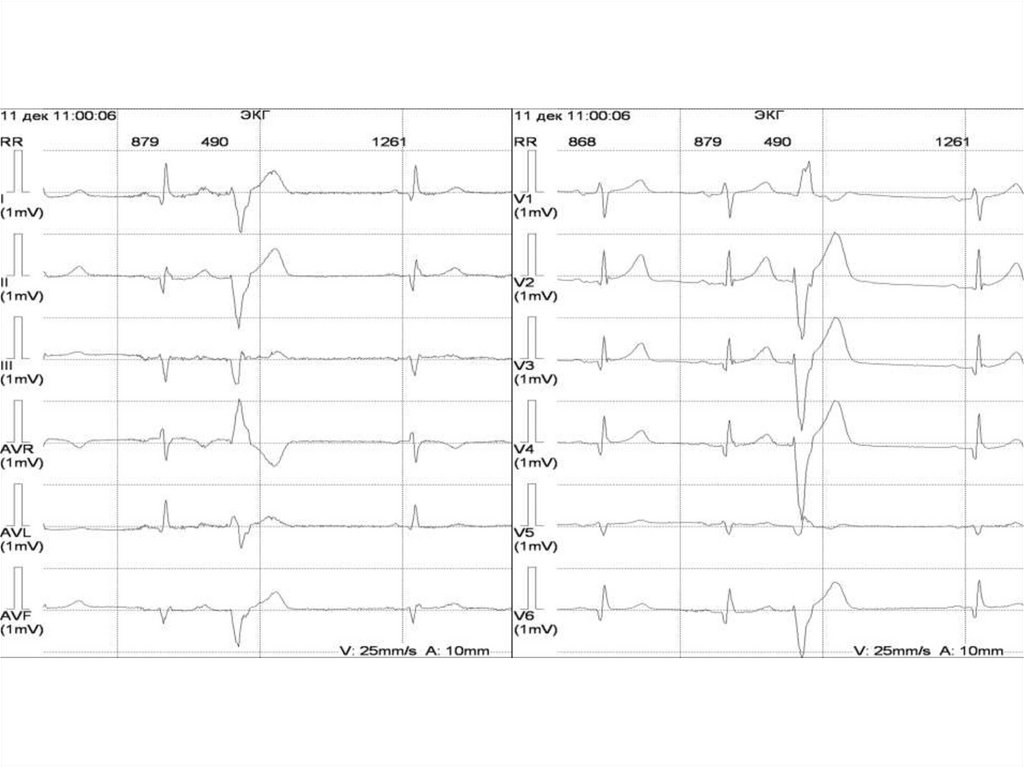

ЭКГ - синусовая брадикардия с ЧСС менее 50 уд/мин, ациклическая

синусовая аритмия, синусовые паузы более 3 секунд, на фоне

правильного ритма выпадает одно или несколько сокращений,

медленное восстановление функции синусового узла после

восстановления ритма (компенсаторная пауза после экстрасистолы более

2 R-R или пауза после восстановления пароксизма тахикардии более 1.5

секунд), синдром тахи-брадикардии (чередование синусовой

брадикардии с пароксизмами мерцательной аритмии или предсердной

тахикардии).